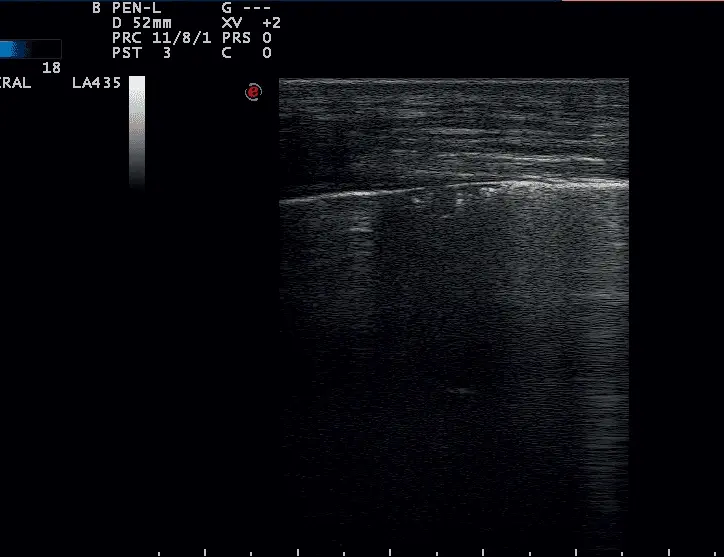

W badaniu USG płuc w siódmej przestrzeni międzyżebrowej w linii przymostkowej lewej był widoczny obszar dużej konsolidacji płuc (do 7 cm głębokości) z bronchogramem powietrznym dynamicznym przechodzącym miejscami w statyczny z widocznymi pułapkami powietrznymi. Obszar konsolidacji był otoczony obszarem zlewających się zespołów śródmiąższowo-pęcherzykowych i pęcherzykowych. Obraz USG wskazywał na zapalenie płuc, najprawdopodobniej na tle zachłyśnięcia (zdj. 2). Została wskazana antybiotykoterapia o szerokim spektrum (bakterie G-dodatnie, G-ujemne i beztlenowce) przez minimum 4–6 tygodni. Poproszono o wykonanie kontrolnego RTG klatki piersiowej po 3–4 tygodniach leczenia. Pacjent otrzymał metronidazol i enrofloksacynę i po 19 dniach pojawił się na kontrolę z nieustającym kaszlem i odkrztuszeniem.